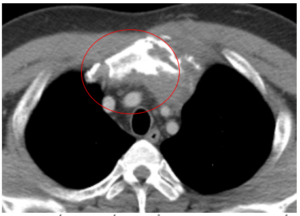

CA LÂM SÀNG: ĐIỀU TRỊ UNG THƯ PHỔI GIAI ĐOẠN MUỘN CÓ DI CĂN NÃO, TUYẾN THƯỢNG THẬN TẠI TRUNG TÂM Y HỌC HẠT NHÂN VÀ UNG BƯỚU, BỆNH VIỆN BẠCH MAI.

CA LÂM SÀNG: ĐIỀU TRỊ UNG THƯ PHỔI GIAI ĐOẠN MUỘN CÓ DI CĂN NÃO, TUYẾN THƯỢNG THẬN TẠI TRUNG TÂM Y HỌC HẠT NHÂN VÀ UNG BƯỚU, BỆNH VIỆN BẠCH MAI. GS.TS Mai Trọng Khoa(1,2), PGS.TS Phạm Cẩm Phương(1,2), BSCKII Lê Viết Nam(1), Sinh viên Lê Minh Phát(2) ...